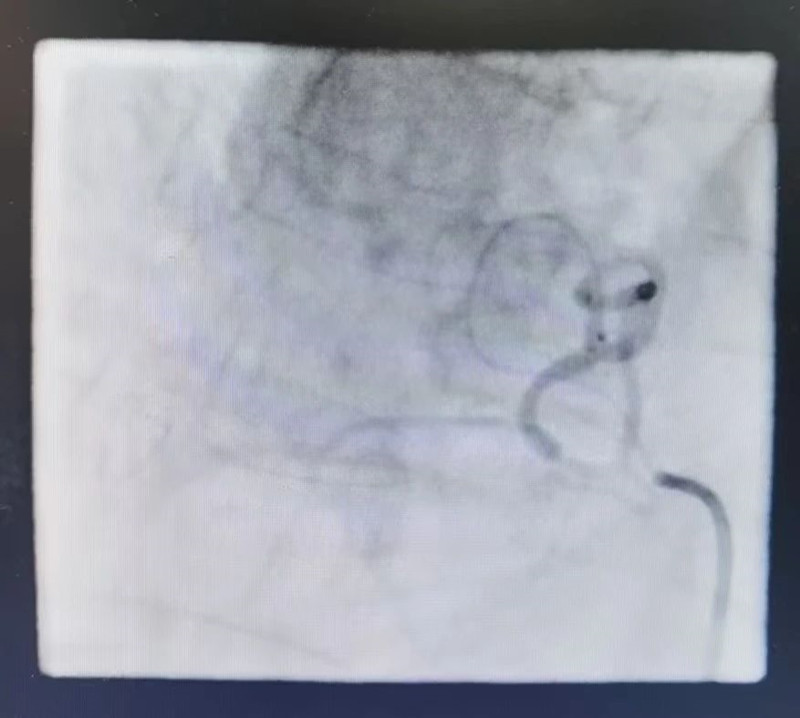

肺门肿瘤染色明显(术前)

术后(染色消失)